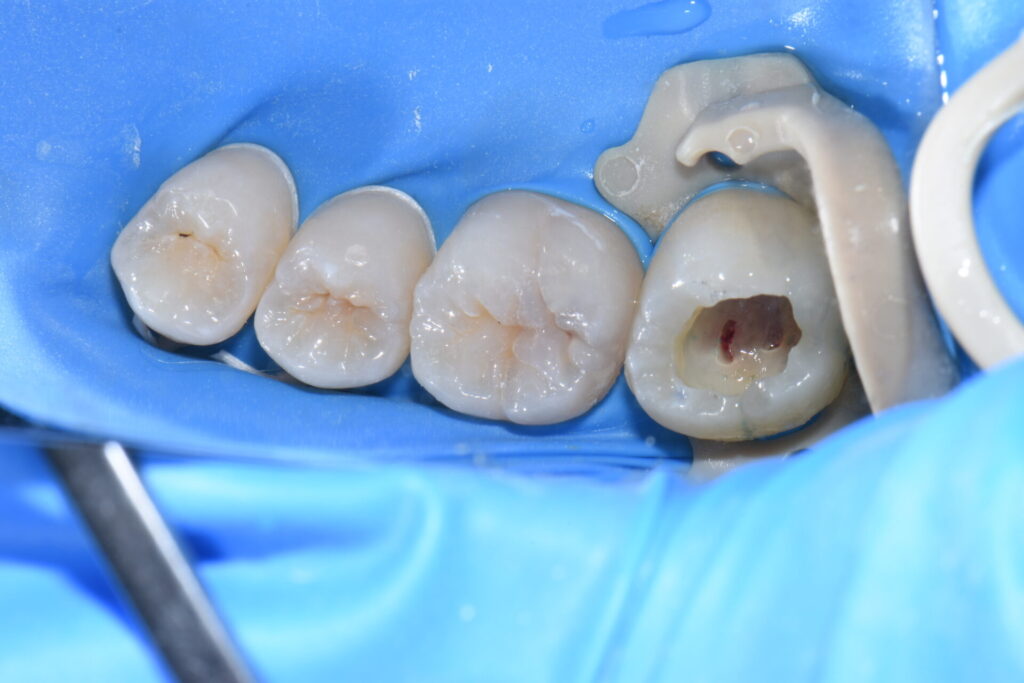

術中 虫歯を除去していくと

術中 神経にまでおよぶ深い虫歯でした。赤く出血しているところが神経です。

当院では虫歯は細菌感染であり綺麗に除去しなけらばならないと考えています。

ラバーダム防湿下で呼気や唾液、口腔内細菌にさらされることなく処置すれば高確率で

神経を温存できます。